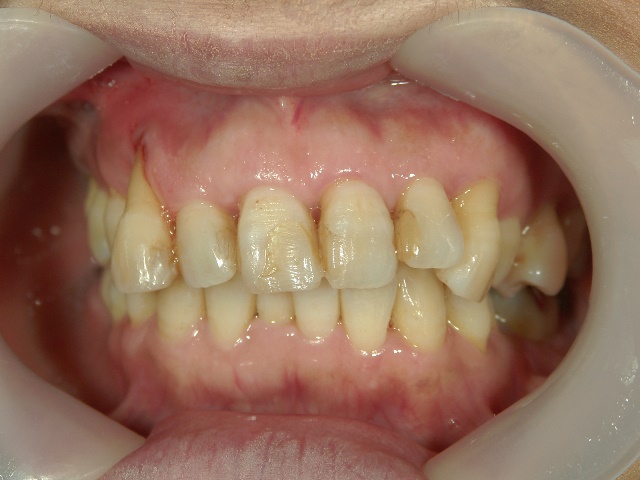

矯正歯科 治療前

矯正歯科(全顎ワイヤー矯正)治療後

全顎ワイヤー矯正 症例(6

)

58歳女性 浜松市浜北区

在住

治療期間11

ヶ月